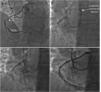

We report the case of a 72-year-old woman with a history of hypertension and dyslipidemia, who came to the outpatient clinic complaining of chest pain. Exercise stress test was positive. Coronary angiography (Figure 1A) by radial approach showed a right coronary artery (RCA) with an anomalous origin at the left sinus of Valsalva, next to the origin of the left main coronary artery, with severe stenosis in the middle segment (arrow). Due to its anomalous origin, selective catheterization of the RCA could not be achieved with any type of guide catheter; the Amplatz-Left-1 allowed the best approach. The use of a catheter extension device (Figure 1B, arrow) enabled selective intubation of the anomalous ostium, advancing the angioplasty balloon and pre-dilation of the stenosis. Subsequently, with the help of the catheter extension device, we implanted a drug-eluting stent in the RCA (Figure 1C) with an excellent final angiographic result (Figure 1D).